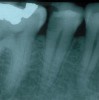

Fig 5. Clinical confirmation of the periradicular diagnosis—chronic apical abscess on tooth No. 19. The tooth is not sensitive to percussion or palpation. A gutta-percha cone is inserted into the sinus tract.

Figure 5

Fig 6. Radiographic confirmation of periradicular diagnosis—chronic apical on tooth No. 19. Note the tracing of the inserted gutta-percha to the etiology. Local anesthesia is generally not required for a sinus tract tracing.

Figure 6

Chronic apical abscess: Radiography typically reveals a radiolucency. Clinically, there is a sinus tract present on the gingival tissue. The draining sinus tract should be traced with a gutta-percha cone and then confirmed radiographically (Figure 5 and Figure 6).